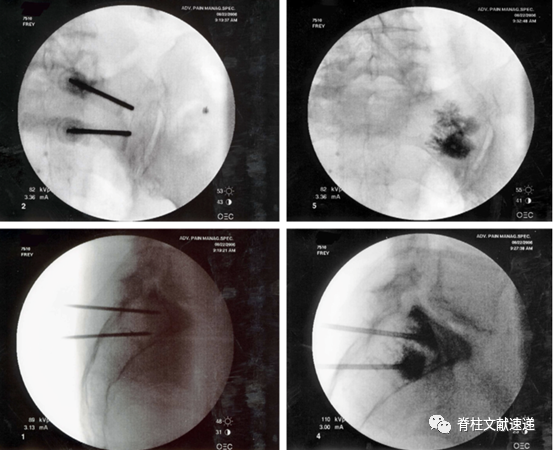

文献中描述了两例骶骨成形术相关骨水泥渗入神经孔的病例,如下图。有一过性 S1 神经炎,在经椎间孔硬膜外注射类固醇后消退。